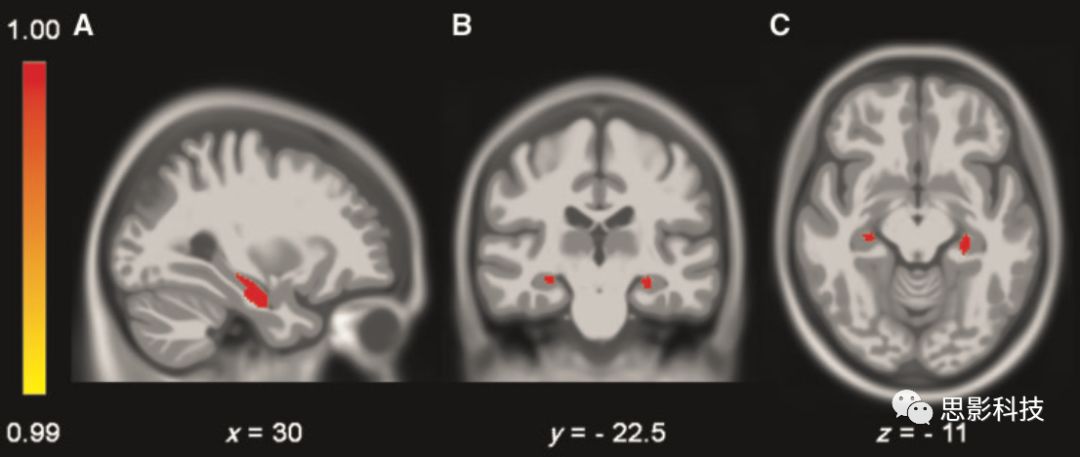

為探討海馬血管供應(yīng)模式是否影響海馬灰質(zhì)密度,研究者將單側(cè)海馬混合血管供應(yīng)被試、雙側(cè)海馬混合血管供應(yīng)被試分別與海馬單血管供應(yīng)模式被試進行雙側(cè)海馬VBM分析比較。無論是單側(cè)還是雙側(cè)海馬混合血管供應(yīng)被試,他們雙側(cè)海馬灰質(zhì)密度均顯著高于海馬單血管供應(yīng)模式被試(表2)。灰質(zhì)密度具有顯著差異的團塊位于海馬前部區(qū)域,為脈絡(luò)膜前動脈分支供血(圖5)。而CSVD與非CSVD組間無顯著差異。2 VBM分析

5:海馬血管供應(yīng)模式相關(guān)的VBM分析。可見海馬混合血管供應(yīng)模式的被試具有較高灰質(zhì)密度,主要位于海馬前部(P<0.001,未校正)。